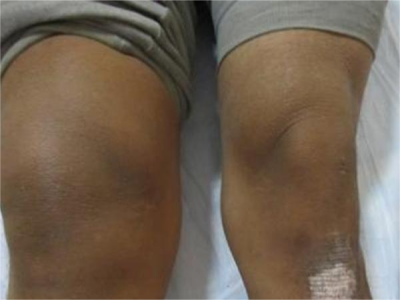

膝关节创伤性滑膜炎是指膝关节外伤后发生的膝关节滑膜无菌性炎症反应,急性损伤性膝关节滑膜炎,可发生于任何年龄。本病以关节疼痛、肿胀为主要临床表现。

膝关节创伤性滑膜炎可表现为局部胀痛,在膝关节完全伸直或属曲时胀痛感更明显,此外,由于局部淤血,可导致局部出现青紫色。局部可逐渐出现关节肿胀,并伴有活动受限、压痛等症状。